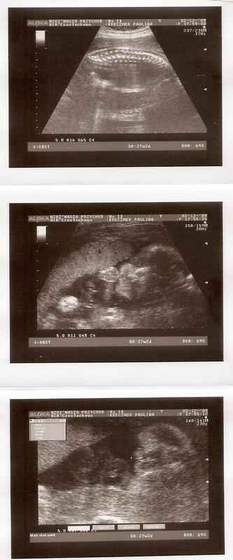

W naszym miescie na polnocy szkocji, o ile nie ma zadnych komplikacji, robia programowo tylko jedno usg (w 13 tygodniu):-(. My bardzo chcielismy znac plec dziecka dlatego pojechalismy do innego miasta (2 godziny drogi) i zaplacilismy £75 za usg ktore mialo byc w 2d ale mila pani doktor zrobila nam prezent na swieta i dostalismy tez zdjatka w 3d (ktore normalnie kosztuja £130) . Teraz przynajmniej wiemy ze bedziemy mieli sliczna i zdrowa coreczke:-) A to nasza Maja

Taka Misia - Pysia Moja:-)